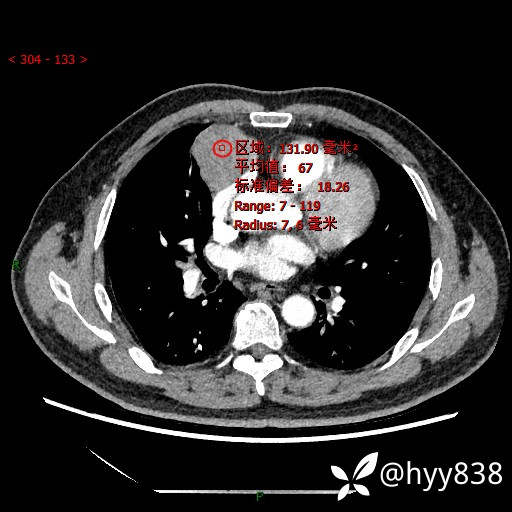

胸部CT平扫

各期CT值